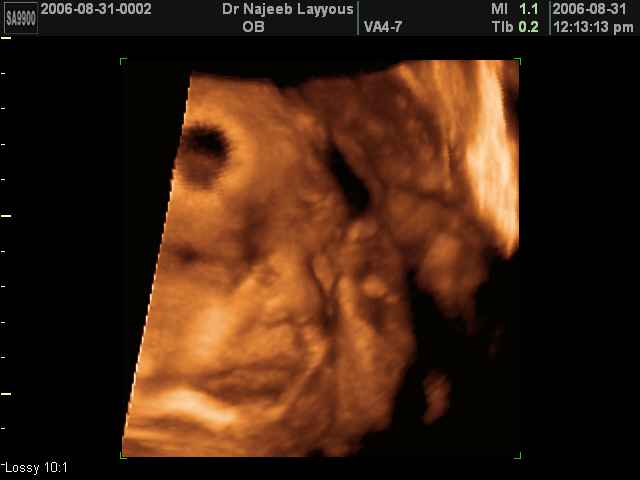

- Fetal Behavior Ultrasound Photos

Ultrasound Photos in 3D showing Fetal Behavior Inside the uterus | Dr N Layyous